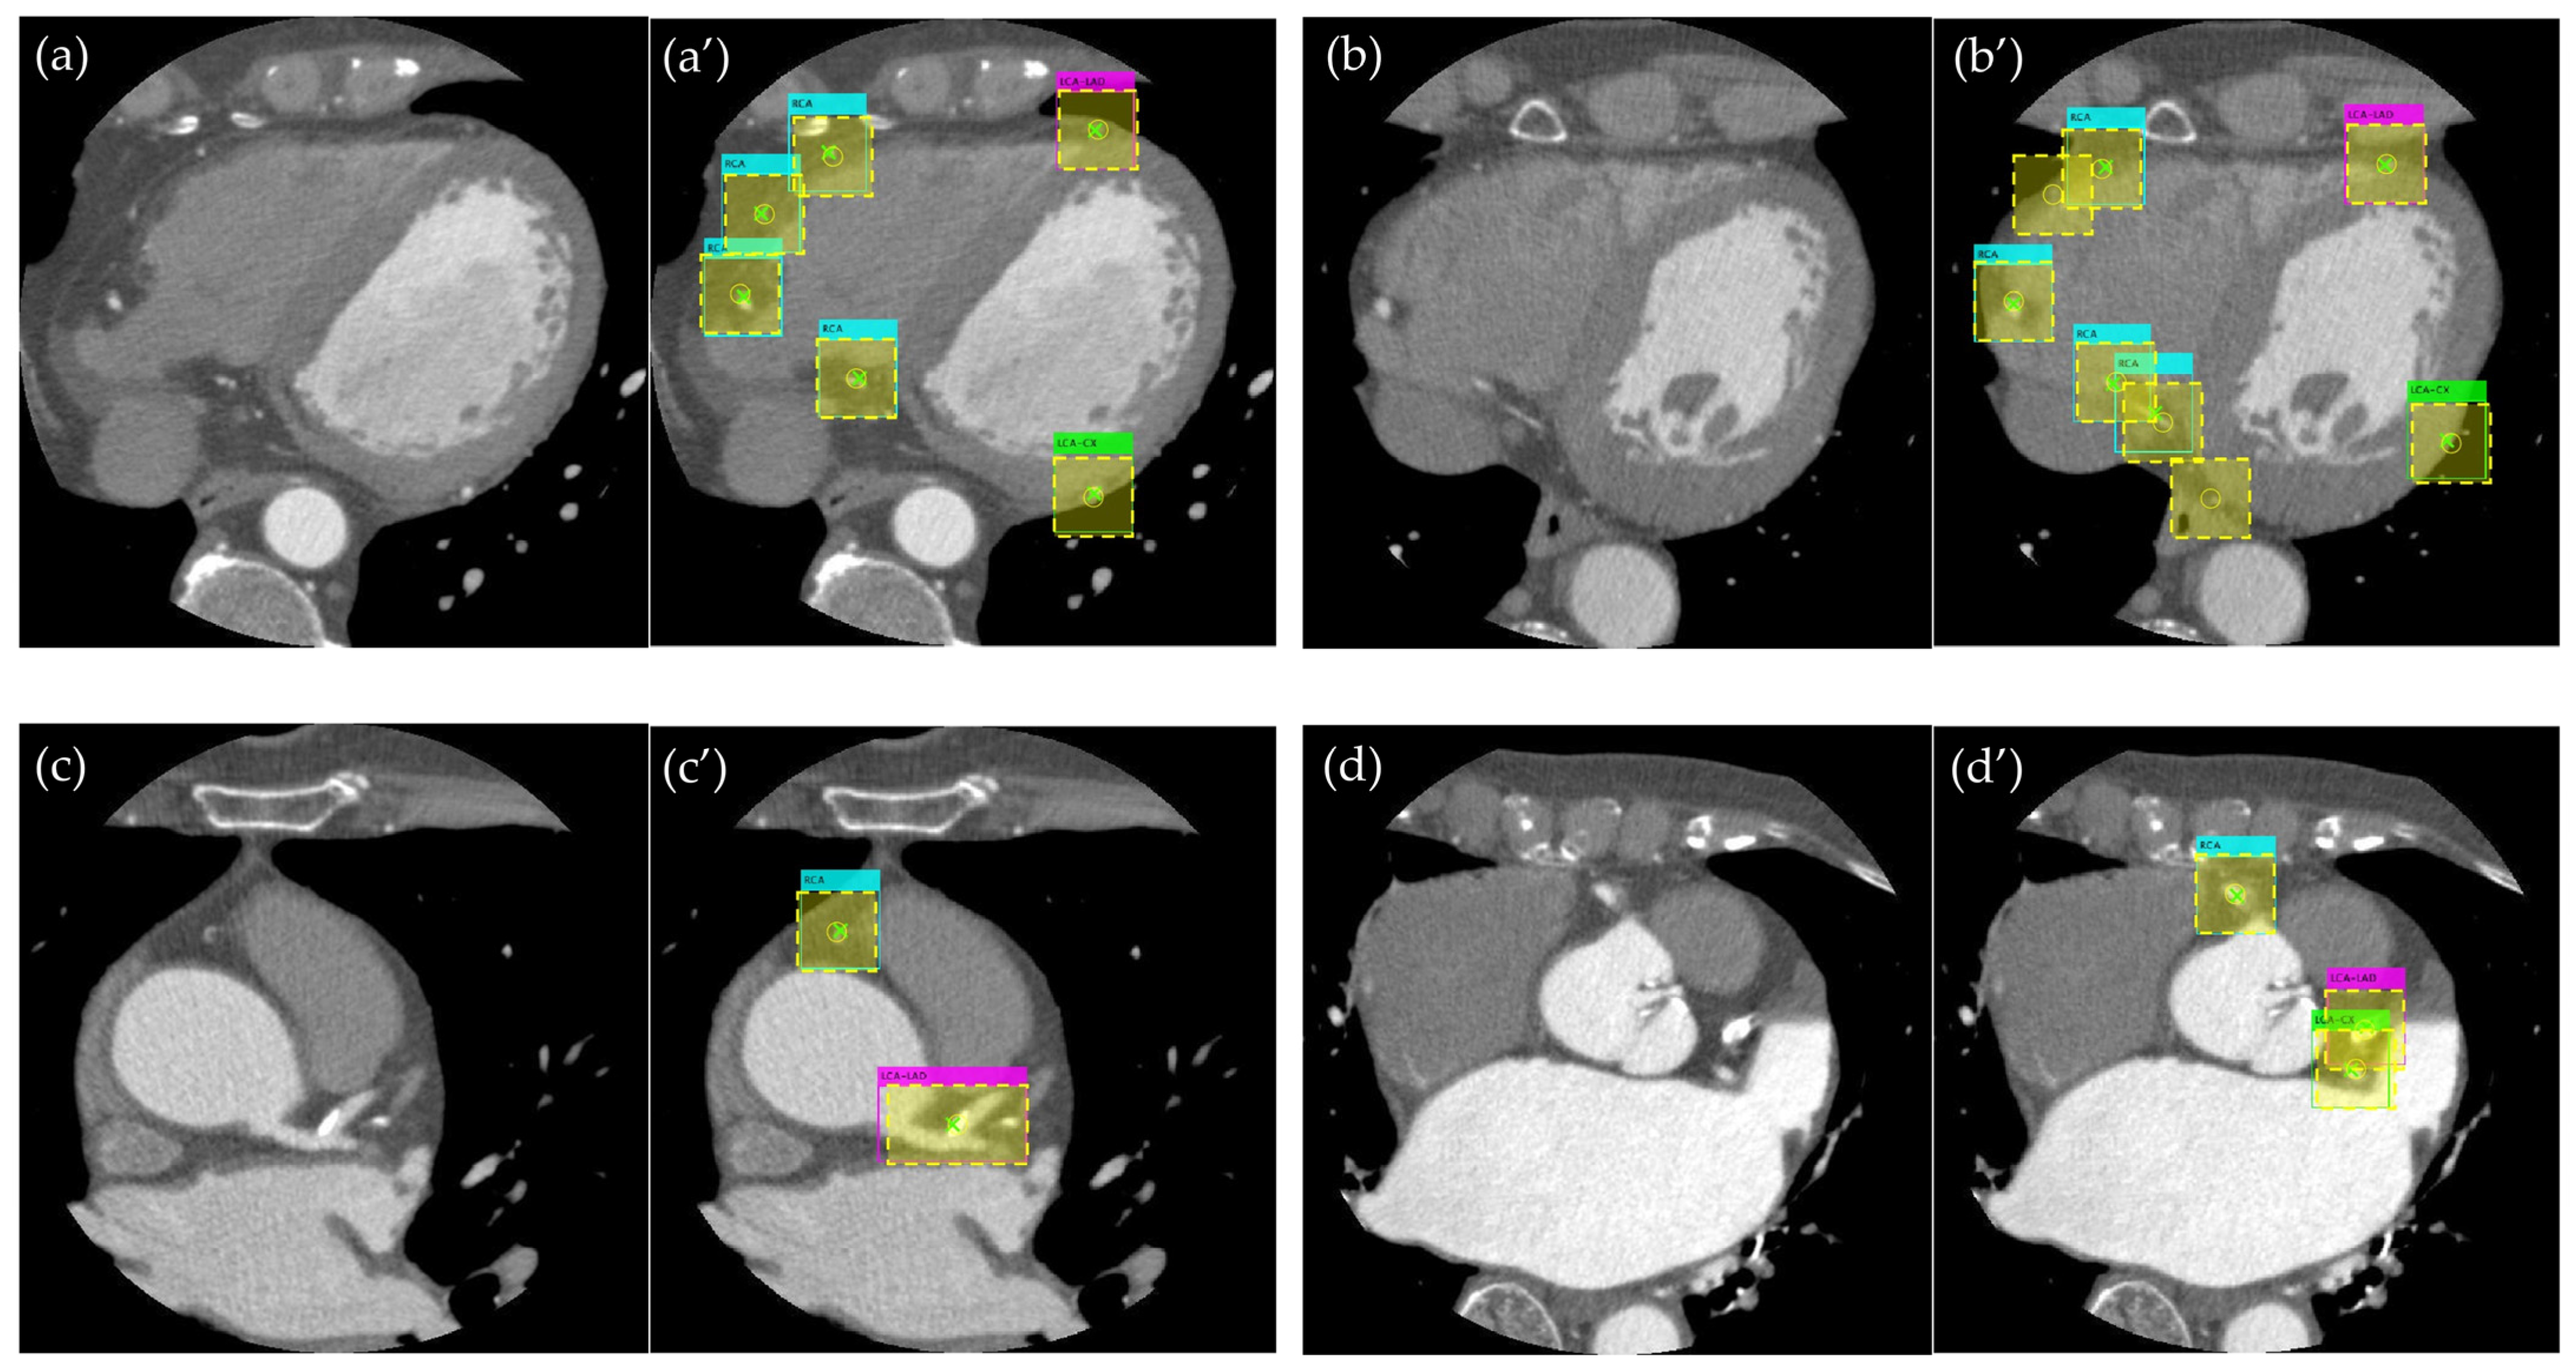

3.1. Evaluation of the Object Detection Model

3.2. Evaluation of Detection Accuracy Using Additional Metrics